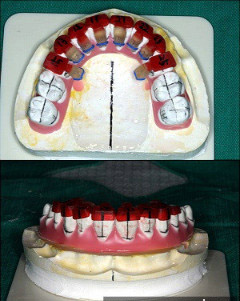

하지만 장치를 설측으로 붙이면서 기존의 치아교정방법과 달리 기술적으로 신경써야하는 부분들이 많다. 일단 치아는 순측에 비해 설측의 구조가 훨씬 복잡하다. 게다가 순측에 비해 설측에 장치를 붙일 때는 시야확보가 어렵다. 이러한 이유 때문에 설측교정의 경우는 교정장치의 접착 위치를 복제된 치아모형상에서 미리 설정해서 접착하는 간접접착방법을 사용한다. 간접접착방법을 사용하면 치료 후의 치아위치를 예상해서 보다 정확하게 교정장치를 장착할 수 있다.

<사진>설측교정장치(위)와 간접접착방법.